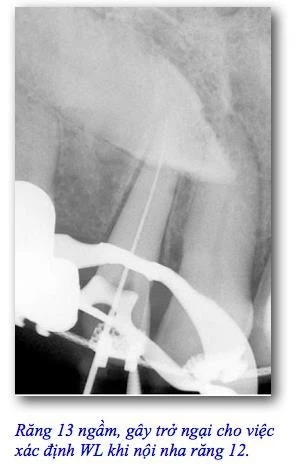

Đây là những công cụ duy nhất dùng để định vị lỗ chóp mà không sử dụng phim tia X vì thế hơn tất cả, nó hữu ích trong những trường hợp mà X-quang không thể hỗ trợ cho chúng ta như trường hợp chóp bị che khuất bởi những vật thể và cấu trúc giải phẫu khác ( ví dụ: răng ngầm, chân răng lân cận, răng cối trên bị che khuất bởi khung gò má…), phụ nữ có thai, bệnh nhân không hợp tác, bệnh nhân bị Parkinson hay người khuyết tật nói chung, bệnh nhân có phản xạ khi đưa sensor hay phim vào miệng… và tất các các tình huống không thể thực hiện bằng tia X.